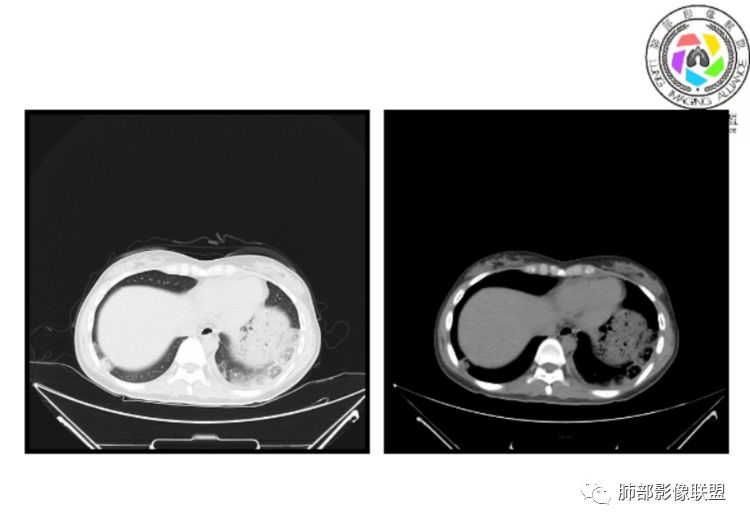

小微:右肺下叶斑片状密度增高影,抗炎治疗6天后复查,双肺下叶出现斑片状密度增高影,排除炎性病变,D2聚体特别高,考虑肺栓塞,肺梗死,建议增强扫描。王开金江津中心医院呼吸科:@岳微-辽宁PLA234医院放射科?支持,患者年轻女性,胸痛主诉,使用雌激素,高危人群,心率快,d二聚体升高,右下叶斑片加肺动脉明显增宽,抗感染无效,要考虑PTE,建议肺动脉ctpa。傅昌瑜:19岁,女性,右侧胸痛2天,发热以中度热为主,D—二聚体升高,肺动脉主干增宽,病灶位于胸膜下,抗感染后增多,近来有服用炔雌醇环丙孕酮片2周期史,诊断:肺栓塞,下一步完善肺CTPA检查。阿仙奴:青年女性,急性起病,胸痛入院,月经不调史,目前服用孕酮片。流感抗体阳性,d二聚体升高,无低氧血症。右肺下叶基底段胸膜下磨玻璃样改变,肺动脉增宽,治疗过程出现发热,复查左下叶胸膜下新发病灶。考虑:肺栓塞(服用孕酮相关)?奔跑的37°Doctor(陆喜红 ) :年轻女性,胸痛 急性病程,有服用雌激素避孕药史(是否有血液循环的改变,高凝状态),实验室D二聚体很高(也是提示血液高凝状态) ,第一次CT,右下肺胸膜下斑片状密度增高模糊影,肺动脉形态密度未见明显异常,抗炎后复查,肺动脉干及其分支,感觉增粗了一点,局部形态有点饱满,双下肺胸膜下片状影增多,锁定肺动脉栓塞应该不会错,建议CTA检查飞鹰行动:青年人,女性,右肺下叶斑片状密度增高影,抗炎治疗6天后复查无好转,,双肺下叶出现斑片磨玻璃影,主肺动脉增粗,结合患者服用的药物和D2聚体特别高,考虑肺栓塞,建议CTA。李:口服避孕药,有危险因素,肺动脉较主动脉增宽,D二聚体增高,胸膜下片状影,考虑肺栓塞;@晨义工张帅,医附属潞河医院呼吸?是否痰中带血很关键,不知有没有张帅:患者入院后第七天出现痰中带血风之子:病程中有发热,D—二聚体升高,肺动脉主干增宽,病灶分布于胸膜下,抗感染后增多,结合服药史诊断:肺栓塞,建议CTPA检查。不支持的地方是没有低氧血症,不明白为什么第二次复查ct双侧乳腺不对称,按理乳腺炎多见于哺乳期张帅:大家方向都在考虑肺栓塞:我提问两个问题:1 周围毛玻璃怎么回事?2左下肺小叶间隔增宽怎么回事?笨丫头:周围的磨玻璃应该考虑是肺梗死后出血渗出,同时合并机化性炎症小叶间隔增宽,我考虑应该是梗死后炎性渗出wonderful:我不支持肺栓塞 不能解释发热原因

水晶石头:患者青少年女性,右侧胸痛2天就诊。有咳嗽,无痰。初次胸部CT:右下肺片状模糊影。入院后经头孢美唑、莫西沙星抗感染治疗6天后复查胸部CT:右下肺病灶加重,且左下肺出现类似病灶。结合其气管镜气道无异常,病程中有发热,D—二聚体升高,近来因月经不调有服用炔雌醇环丙孕酮片史。诊断考虑良性非感染性。肺栓塞可能性大,鉴别血管炎及子宫内膜肺异位可能。流心明智:女性,19岁,右侧胸痛2天,中度热为主,D—二聚体升高,影像:肺动脉主干小于29mm,病灶位于右下肺胸膜下,斑片影,胸膜侧宽基底,抗感染后增多,左下肺亦出現类似病灶,似有反晕、融冰征。近来有服用炔雌醇环丙孕酮片2周病史,考虑诊断:肺栓塞。具体性质及发病机制有待进一步检查。尘缘:@吴永丽 灌云县医院 呼吸?应该是的,左下肺的磨玻璃影像后面也支持有出血改变所以可能就是一个子宫内膜异位出血合并感染

没意见:同意各位老师高见,临床D二聚体比这个高的多了,这个指标只能作为筛选条件,就这个病例来说,指向性还是比较明显的,没看出还有别的可能wonderful:d2聚体阴性有排除意义 阳性与数值意义不大天涯:感染有,是不是和栓塞有关?还要CTA,子宫内膜异位思路很好不倾城不可爱:会不会子宫内膜异位症呢采莲:青年女性,有口服避孕药病史,双下肺胸膜下多发斑片磨玻璃影,有融冰征,二聚体高,还是首选肺栓塞可能性大。至于子宫内膜异位症见得少。崇军:第一次点晕征,六天以后加重,而且左下肺病灶明显增大,磨玻璃,pct正常,抗感染无效,所以感染性病变排除。肿瘤性病变,太年轻,暂排。血管炎,化验为阴性。少见病子宫内膜移位不会六天以后加重。结合化验指标,还是肺栓塞可能南边:曹老师考虑子宫内膜异位症?有没有考虑肺栓塞的?我们下一步该如何处理?

1、一个或多个胸膜下斑片高密度影(梗死、出血、肺不张、肺水肿、炎性渗出),典型为胸膜下楔形影 ,尖端指向肺门

3.影像:病变胸膜下多发斑片影,提示与血管有关,早期病变为渗出,应该是早期的炎性渗出,病灶抗感染治疗后实变区增多、变大,临床症状又出现咯血,CT上应该合并了肺泡出血、梗死、肺不张及肺水肿;